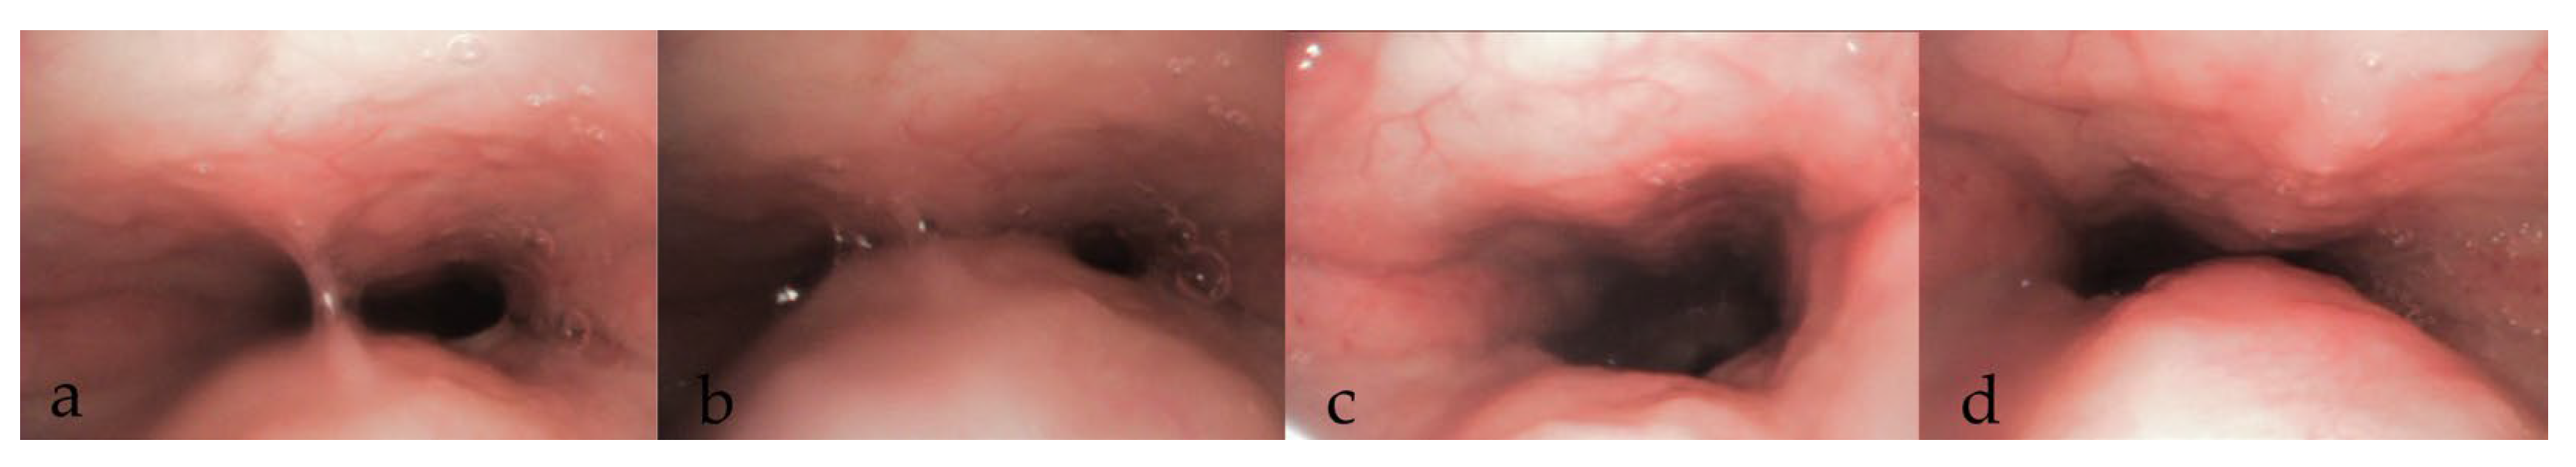

3.3. During DISE (Figure 1)

3.3.8. Documentation